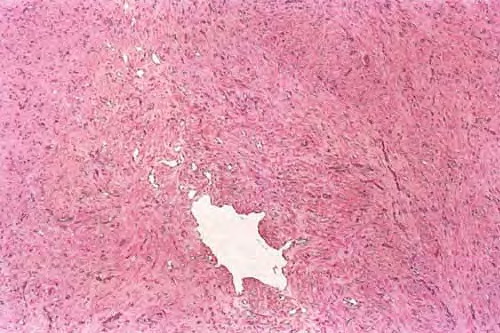

Angioleiomyoma =العضلوم الوعائي